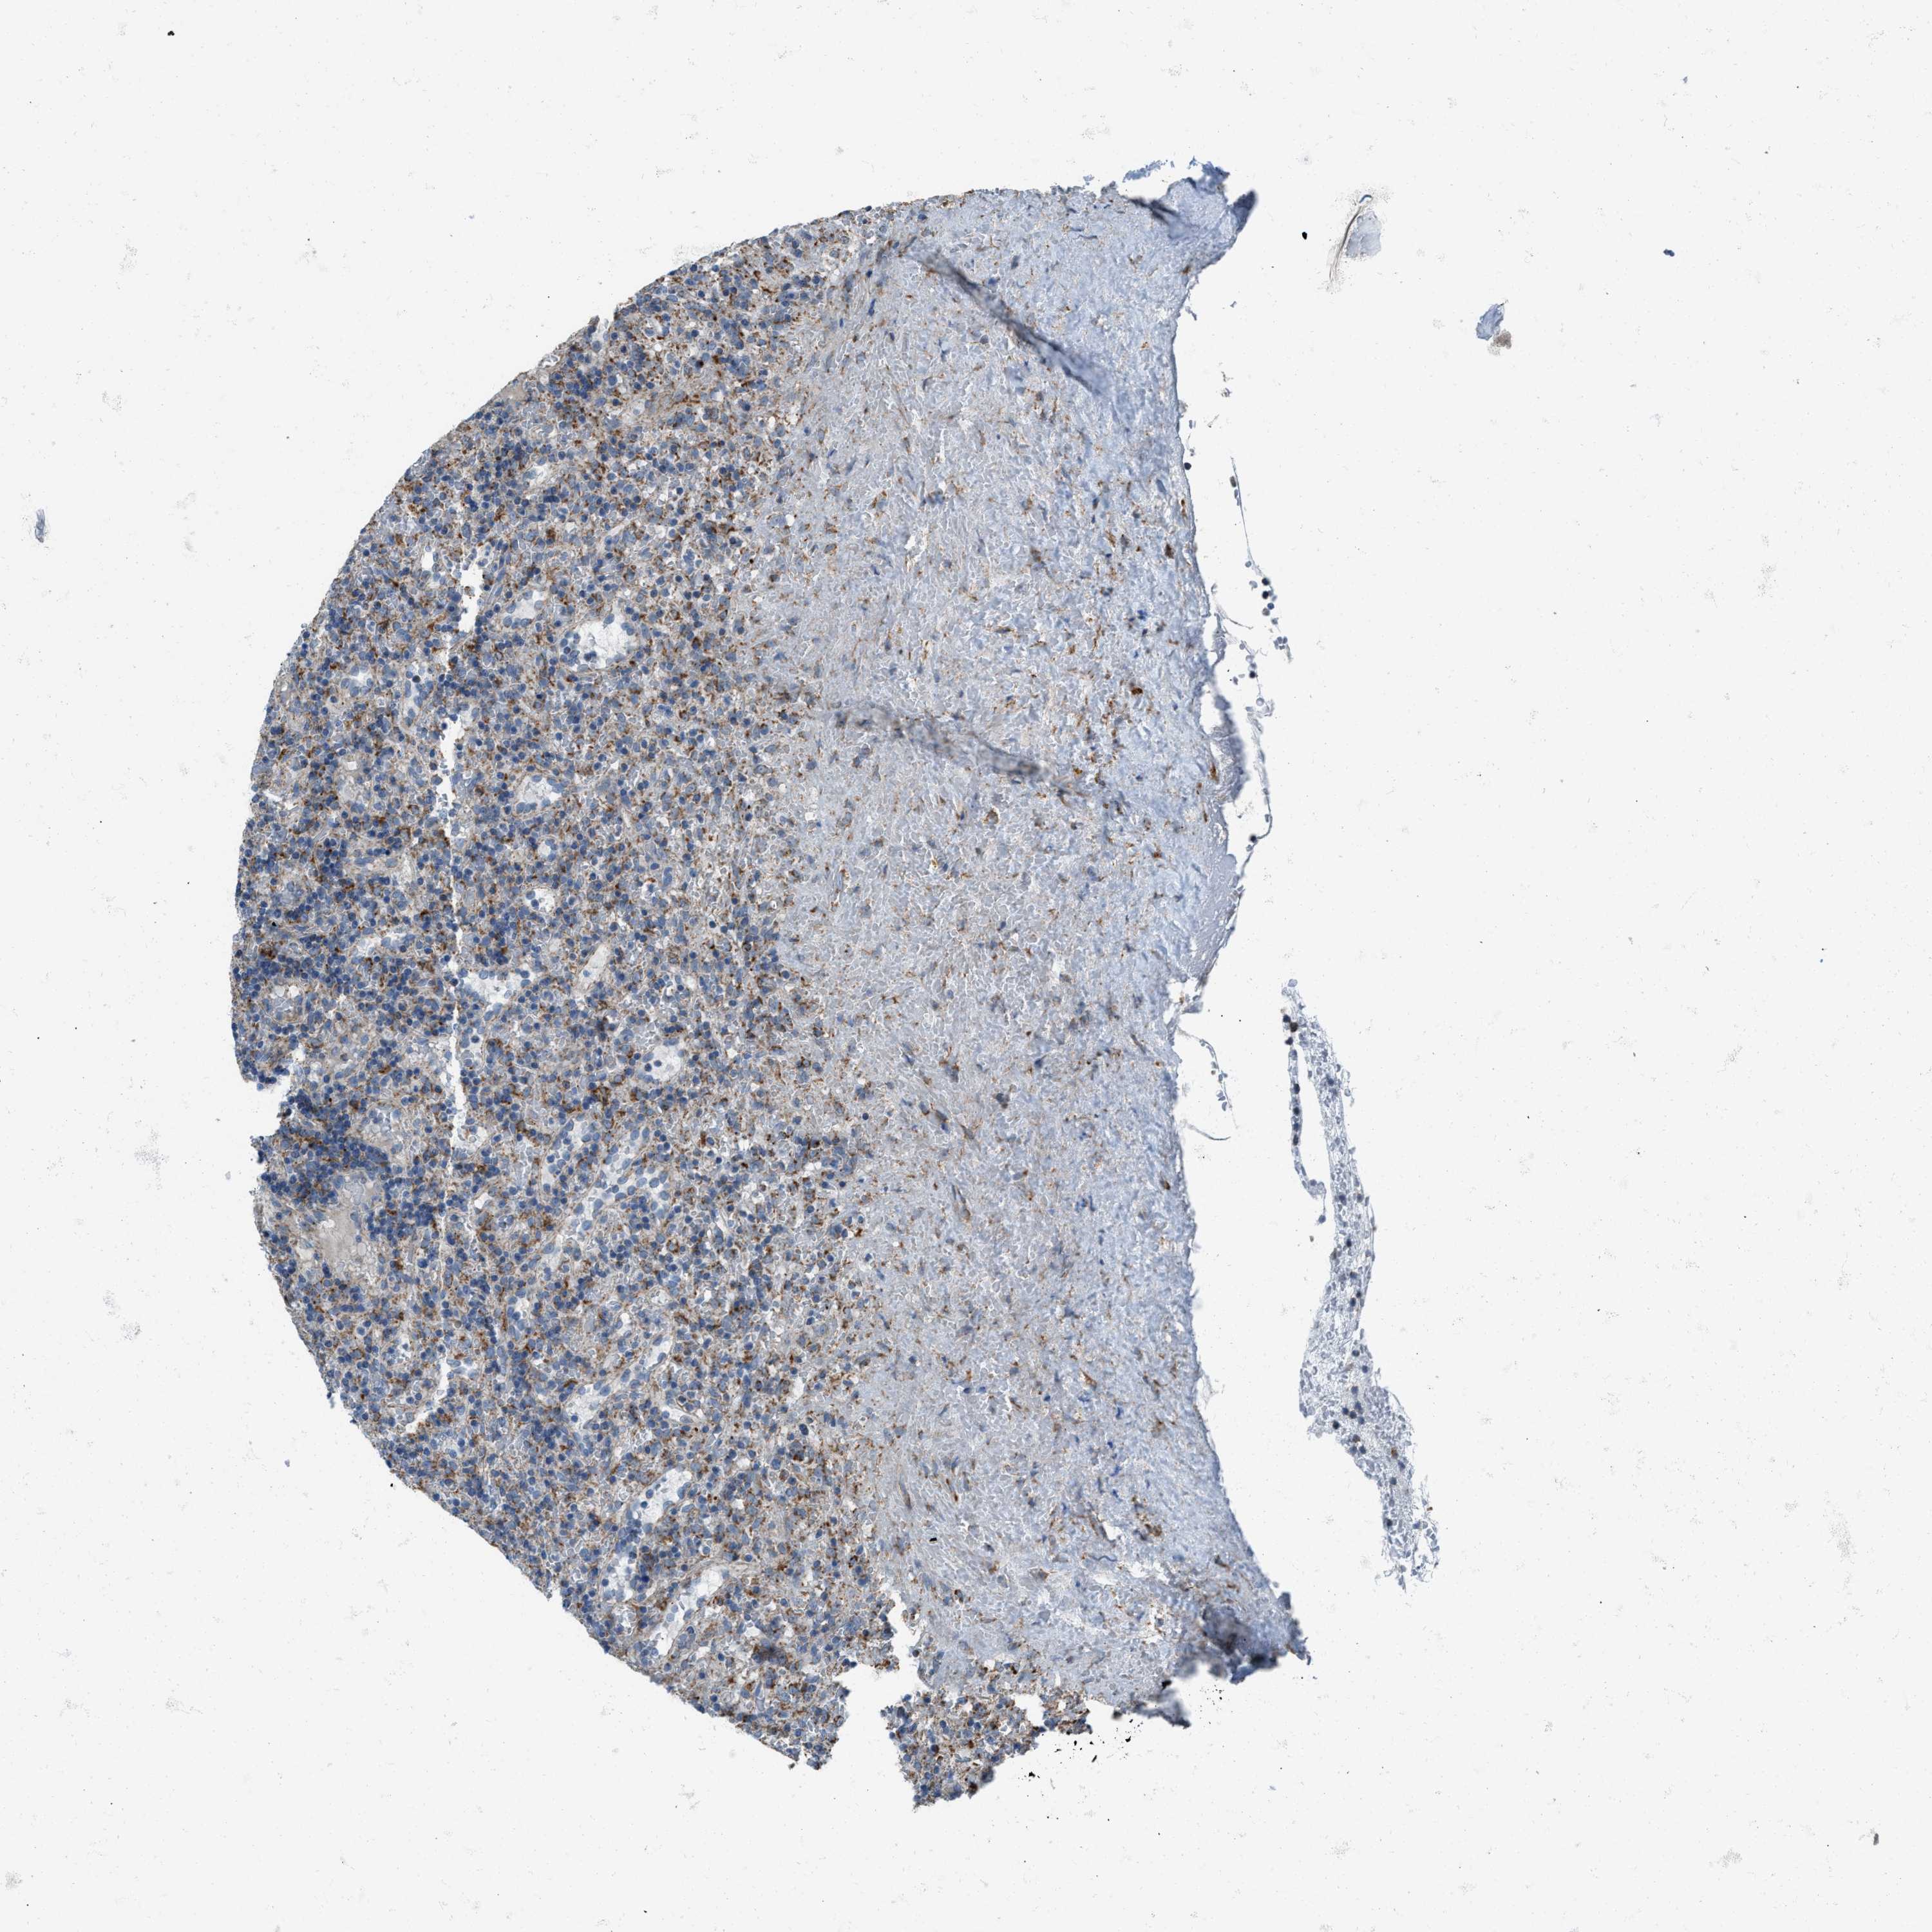

CANCER LYMPHOMA Show tissue menu

LYMPHOMA - Protein expressioni

A mouse-over function shows sample information and annotation data. Click on an image to view it in a full screen mode. Samples can be filtered based on level of antibody staining by selecting one or several of the following categories: high, medium, low and not detected. The assay and annotation is described here.

Antibody stainingi

Antibody staining in the annotated cell types in the current human tissue is reported as not detected, low, medium, or high, based on conventional immunohistochemistry profiling in selected tissues. This score is based on the combination of the staining intensity and fraction of stained cells.

Each image is clickable and will lead to virtual microscopy that enables deeper exploration of all samples and also displays staining intensity scores, fraction scores and subcellular localization as well as patient and tissue information for each sample.

Antibody HPA016552

Staining

High

Medium

Low

Not detected

Intensity

Strong

Moderate

Weak

Negative

Quantity

>75%

75%-25%

<25%

None

Location

Nuclear

Cytoplasmic/membranous

Cytoplasmic/membranous,nuclear

Hodgkin's disease, NOS

Malignant lymphoma, non-Hodgkin's type, High grade

Malignant lymphoma, non-Hodgkin's type, Low grade